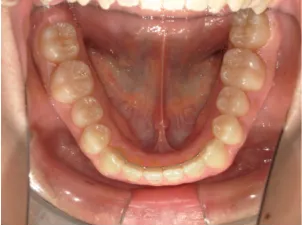

治療前①小5:スタート

| はじめのご相談 | 凸凹になりそうと一般歯科の先生に言われたのでみてほしい |

|---|---|

| カウンセリング・診断結果 | 下あごが後退しているタイプの出っ歯で、過蓋咬合で下あごが前に成長しにくいタイプの顔立ちです。 上の歯列弓が小さめで前歯に凸凹があります。 口元が閉じにくい口唇閉鎖不全があります。 *上記に対する治療の流れを説明し(拡大・前歯の並べ替え→出っ歯の改善→モノブロック装置(筋機能的咬合誘導装置)→必要によりマルチブラケット法)、以下の治療を提案しました。 |

| 行ったご提案・診断内容 | 成長期に行う治療と咬合治療をご提案しました。 成長期治療(成長時期にお口の環境を整え、適正な成長を促す治療)で、 ①歯列弓形態の修正、拡大と前歯を並べる。 ②出っ歯を治す専用の装置を使用する。 ③・MFT:舌や口唇などが正しい動きやポジショニングで機能し、鼻で呼吸できるようにする練習、毎日おうちで習慣づくように続けてもらいます。 ④拡大による顎顔面の適正な成長効果で口元を改善する(写真③)。 |